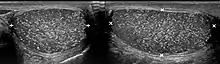

Cause

The cause is unknown, but this condition has been associated with testicular cancer in a small group of individuals, cryptorchidism, mumps, infertility and intraepithelial germ cell neoplasia. Classic testicular microlithiasis is defined as five or more echogenic foci per view in either or both testes, and limited testicular microlithiasis defined as one or more echogenic foci that do not satisfy the criteria for classic testicular microlithiasis. In 80% of cases, both testicles are affected.